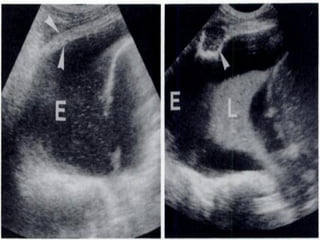

PericardialTamponade

 Remember tamponadeis a clinical diagnosis based on

patient’s haemodynamics and clinical picture.

 Ultrasound may demonstrate early warning signs of

tamponade before the patient becomes haemodynamically

unstable.

 Haemodynamic effects

 Its PRESSURE NOT SIZE THAT COUNTS!

 Rate of formation affects pressure-volume relationship and

is therefore more important than volume of fluid.

Tamponade using ultrasound

 A moderate-large effusion.

 Right atrial collapse

 Atrial contractionnormal in atrial systole

 Collapse throughout diastole or inversion is abnormal.

 RV collapse during diastole when meant to be filling

(‘scalloping’ seen)

 Whats seen in the IVC…

PericardialTamponade  Remember tamponadeisa clinical diagnosis based on patient’s haemodynamics and clinical picture.  Ultrasound may demonstrate early warning signs of tamponade before the patient becomes haemodynamically unstable.  Haemodynamic effects  Its PRESSURE NOT SIZE THAT COUNTS!  Rate of formation affects pressure-volume relationship and is therefore more important than volume of fluid.

• 76.

Tamponade using ultrasound A moderate-large effusion.  Right atrial collapse  Atrial contractionnormal in atrial systole  Collapse throughout diastole or inversion is abnormal.  RV collapse during diastole when meant to be filling (‘scalloping’ seen)  Whats seen in the IVC…